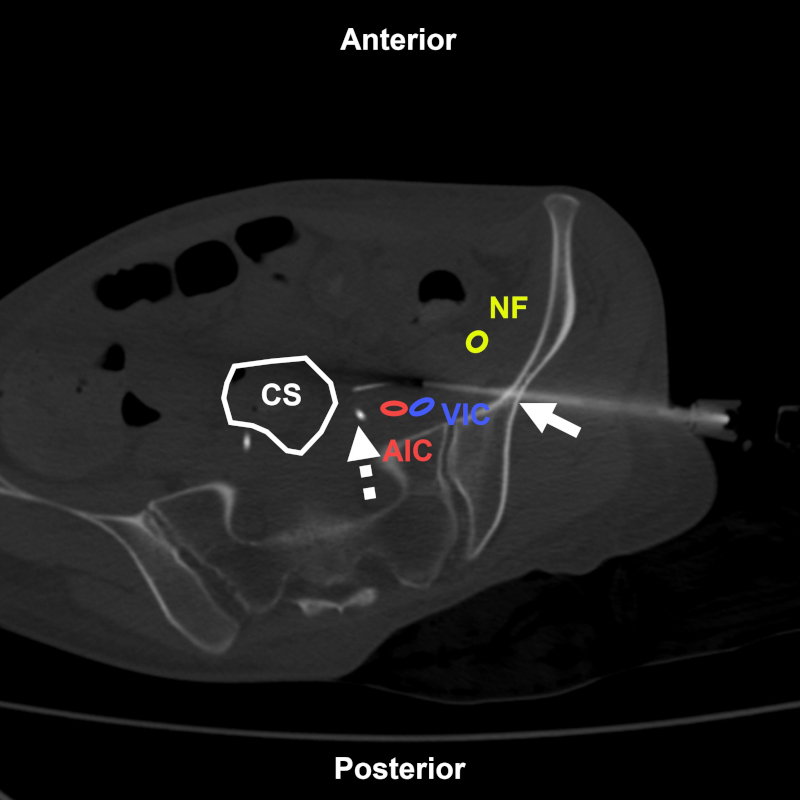

Figura 25

Mujer de 27 años con antecedentes de cáncer de cuello uterino con nódulos abdominales en control oncológico. BP coaxial con abordaje transilíaco (flecha) bajo TC. Estructuras a evitar: NF: nervio femoral; AIC: arteria ilíaca común; VIC: vena ilíaca común; CS: colon sigmoide. Uréter con catéter doble J (flecha discontinua). Aguja utilizada: Jamshidi 11 G con Supercore 20 G (sistema semiautomático). Diagnóstico final: infiltración por carcinoma escamoso de alto grado.